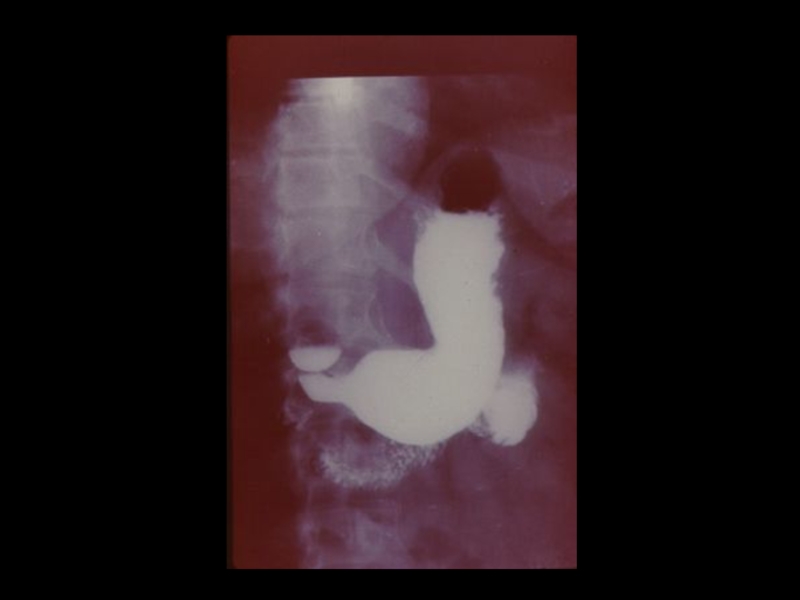

Слайд 39Йодсодержащие рентгеноконтрастные вещества:

I. Ионные - трийодзамещенные

1) Водные (

урографин, уротраст, верографин,

йодамид, триомбраст )

2) Масляные ( Йодолипол, майодил, лимфотраст)

II.Неионные ( 1974 )

1) Циклические трийодзамещенные неионные

мономеры ( Амнипак, омнипак, имагопак)

2) Неионные гексайодированные димеры

( молекула состоит из 2-х бензольных колец с

атомами йода)

- Везипак ( для ангиографии)

- Иотролан ( для миелографии )